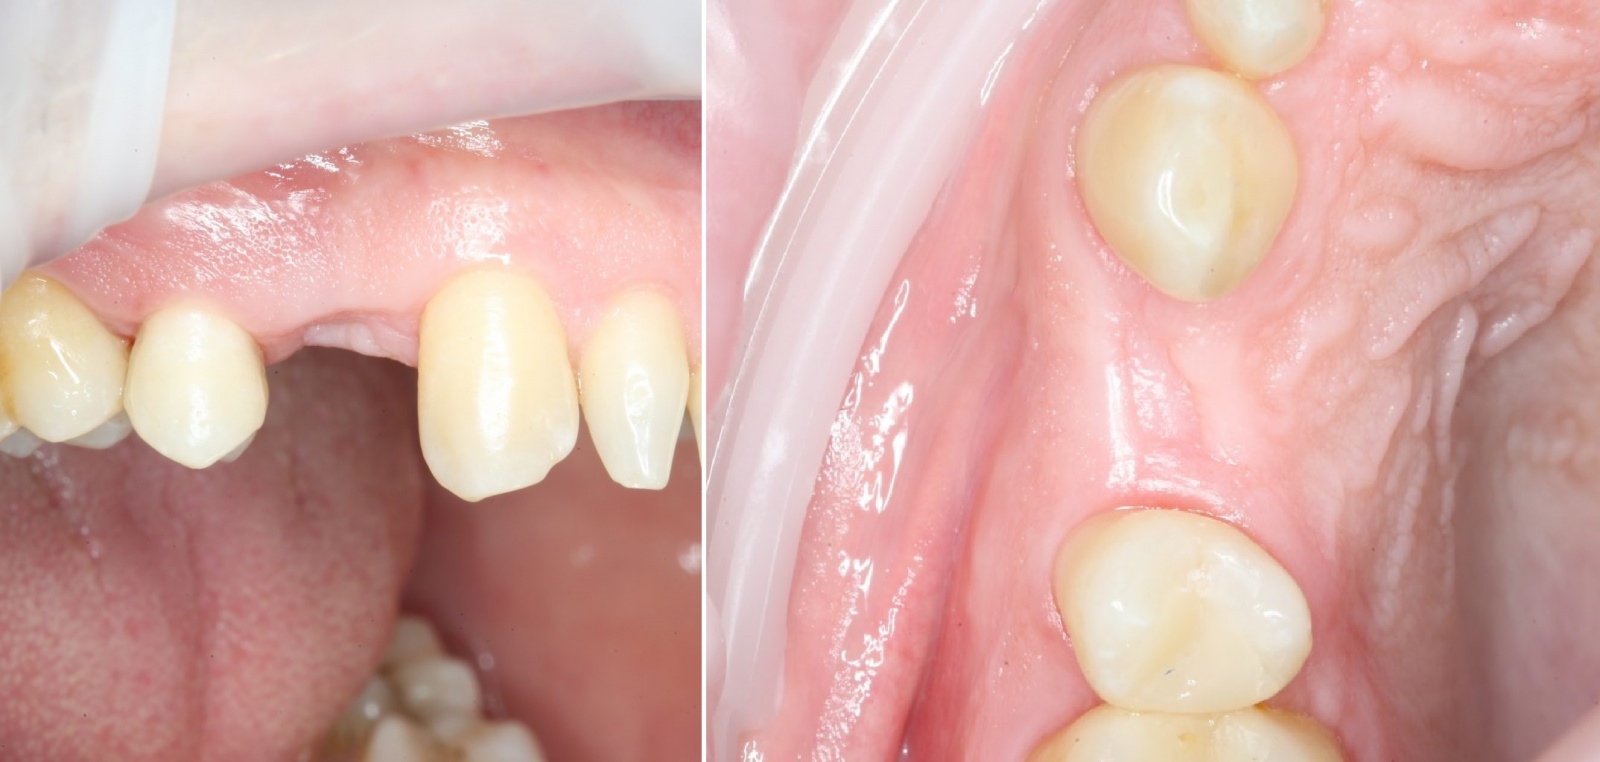

В данном случае, объёмов костной ткани достаточно для стабилизации оптимального по размеру имплантата, а качество десны делает возможным формирование эстетического контура без дополнительных процедур: